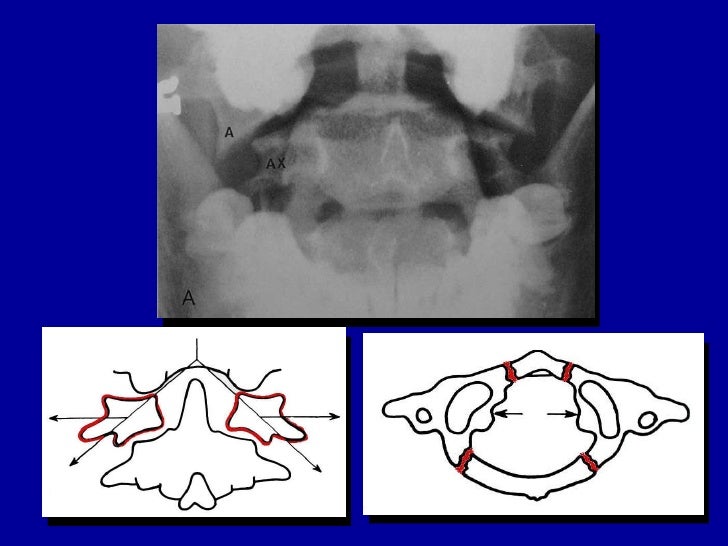

CT scan or X-ray images are evaluated for the presence or absence of directly visible fractures. In addition, indirect signs of injury by the vertebral column are incongruities of the vertebral lines, and/or increased thickness of the prevertebral space: